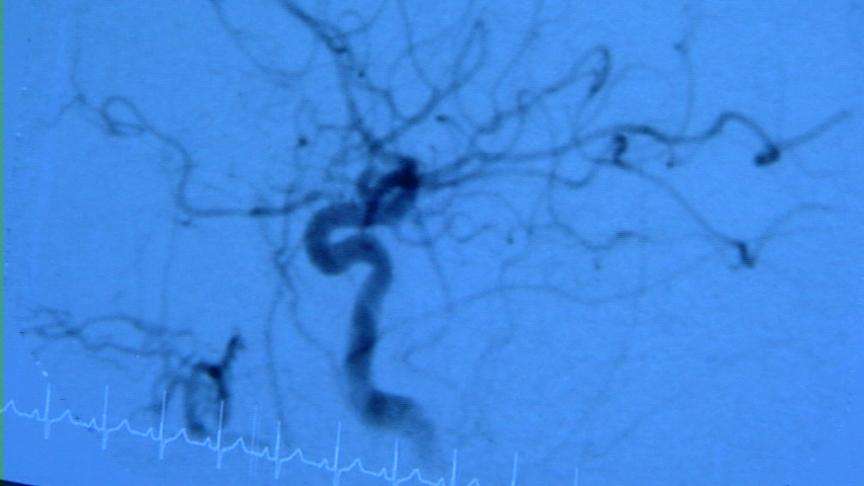

The data shows ultrafine air pollutants, which are already highly reactive molecules, generate what are called free radicals when they find their way into the blood vessels.

Utah cardiologist Dr. Jeffrey Anderson says this latest University of Southern California study is just more ammunition researchers have now collected. The damage to vessels and the heart, he says, becomes all too obvious. "And they are so small that they can exchange into the circulation of the blood as they pass through the lungs, circulate around, and cause injury to the blood vessels as they go along. That induces inflammation," he said.